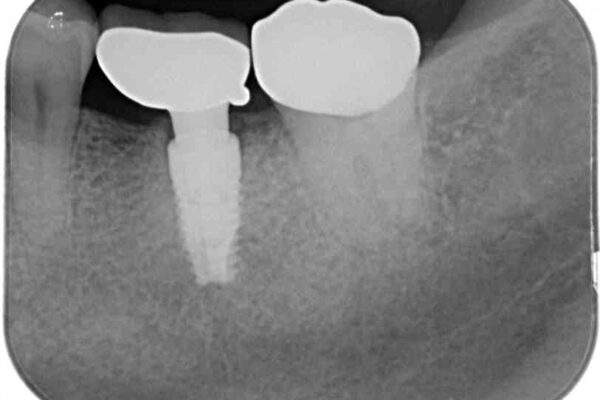

銀歯の装着されている奥歯がしみるとのことで来院された患者様です。

治療計画

銀歯周辺の歯が欠けており、むし歯も進行している状態であったので、オールセラミッククラウンにて補綴治療を行うこととしました。

治療前

• しみる奥歯 オールセラミッククラウンによる補綴治療 治療前画像